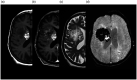

Cavernous malformations are angiographically occult vascular malformations. They are often associated with a developmental venous anomaly through poorly understood mechanisms. We present an unusual case of a gradually enlarging cavernous malformation associated with a developmental venous anomaly with arteriovenous shunting, suggesting venous hypertension or reflux as a potential cause of progressive growth.